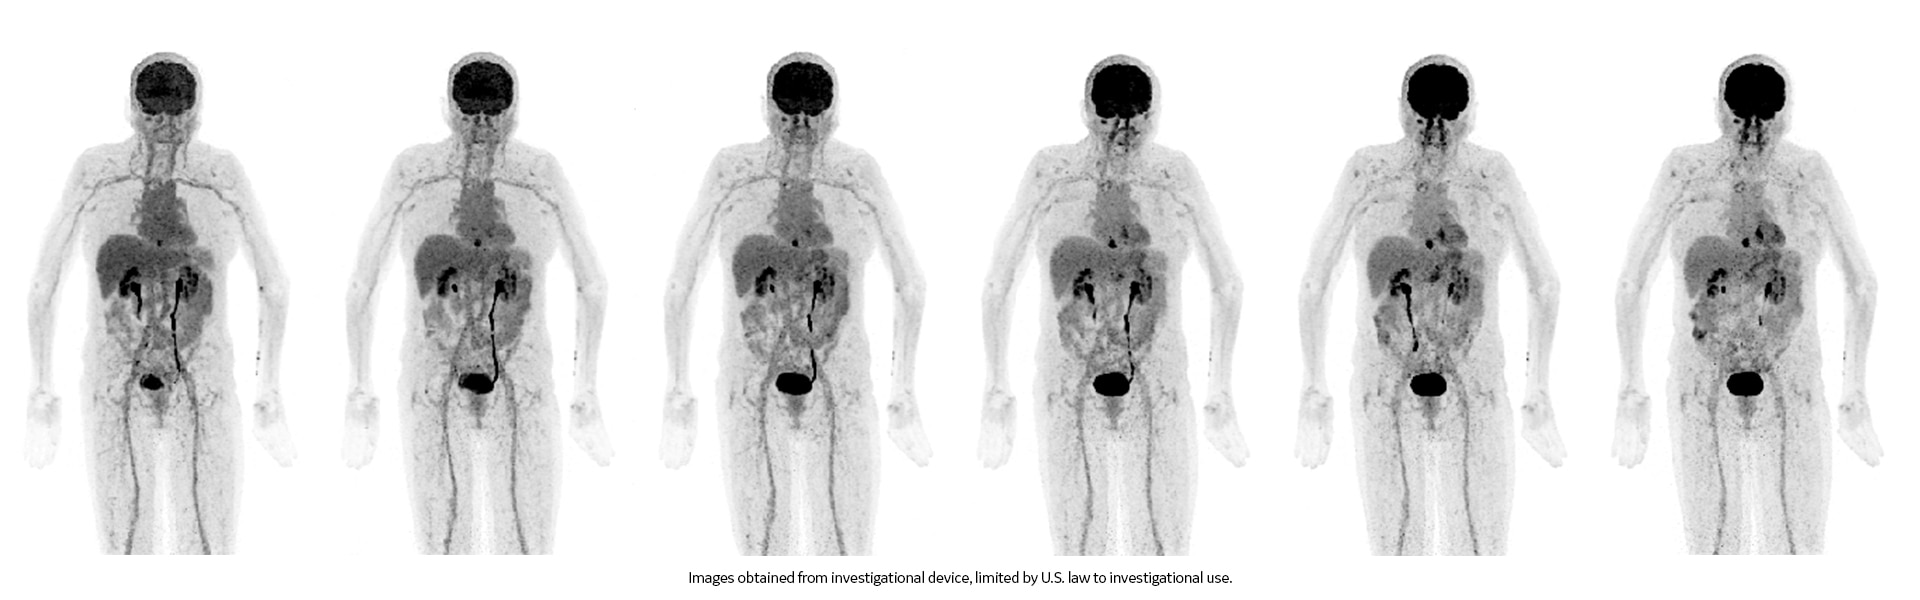

Vea exactamente lo que necesita ver

Imágenes clínicas

Varias lesiones pequeñas en las piernas y por el cuello.

La lesión en el oído derecho mide 3,5 mm en el TC. Tumor en la cadera que atraviesa el hueso.

Medición cervical derecha de 6 mm.

Acné observado en la espalda.

Pulmón derecho, ingle derecha y tumor detrás de la rodilla derecha.

Cáncer de cabeza y cuello.

Posterior a la radioterapia, progresión del cáncer. Cáncer de mama pequeño.

Ganglios linfáticos ávidos de FDG en la axila izquierda (vacunación contra la COVID-19).